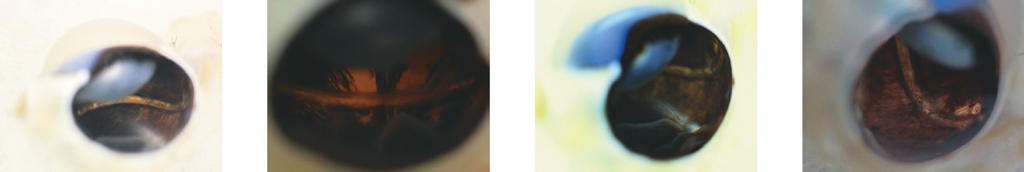

При выполнении биомикроскопии переднего сегмента глаза на 1, 3, 7 и 15-е сутки после операции выявляли смешанную инъекцию глазного яблока, а также умеренный локальный хемоз в области послеоперационной раны (рис. 5). В течение первых трёх суток из конъюнктивальной полости наблюдалось незначительное серозное отделяемое. Воспалительные явления полностью разрешались в течение 7–10 дней на фоне стандартной местной противовоспалительной и антибактериальной терапии. Видимые слизистые и кожные покровы в течение всего периода наблюдения сохраняли естественный цвет и блеск.

Рис. 5. Передний сегмент глаза экспериментального животного на 1–3-е сутки после оперативного вмешательства

Fig. 5. Anterior segment of the experimental animal’s eye on Days 1-3 after surgery

За весь период наблюдения признаков воспаления увеального тракта отмечено не было. Роговица, влага передней камеры оставались прозрачными, радужка в цвете и рисунке не изменялась на протяжении всего периода наблюдения. Зрачковые реакции на свет были сохранны, оптические среды прозрачные, рефлекс с глазного дна розовый (рис. 6).

Рис. 6. Передний сегмент глаза экспериментального животного на 15-е сутки после оперативного вмешательства

Fig. 6. Anterior segment of the experimental animal’s eye on Day 15 after surgery